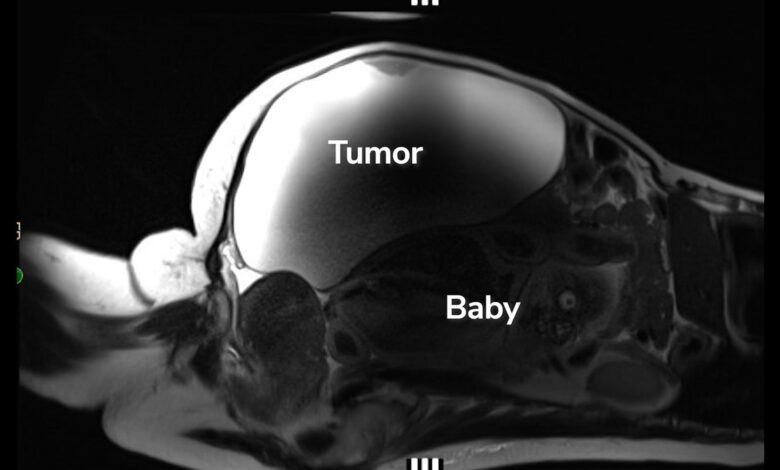

Lopez dorazila do nemocnice s velmi vysokým krevním tlakem, a když se lékařský personál pustil do jeho léčby, provedli také krevní testy a skenování těla, včetně MRI a ultrazvuku. Tehdy zjistili, že Lopez nosí vzácné břicho mimoděložní těhotenství. Dítě se nacházelo v blízkosti jater a jeho záda spočívala napůl na horní části dělohy.

„Bylo to dítě, které jí rostlo v břiše za tou hmotou, co všechno tlačilo ven,“ Dr. John Ozimeklékařská ředitelka porodnice a oddělení mateřské a fetální péče v Cedars-Sinai, uvedla ve videu. „Takže to je důvod, proč nevěděla, že je těhotná.“

Dodal, že „těhotenství tak daleko mimo dělohu, která žije, je do značné míry bezprecedentní.“